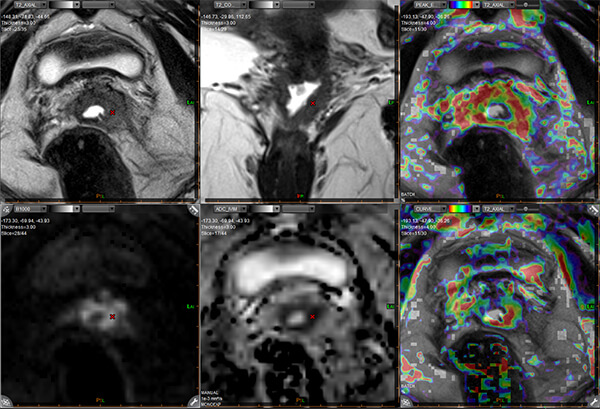

Πολυπαραμετρική απεικόνιση ενδομητρίου - εκτίμηση έκτασης - τοπική σταδιοποίηση

Συνδυάζοντας τις ειδικές τεχνικές της μαγνητικής τομογραφίας εφαρμόζουμε αυτό που ονομάζεται πολυπαραμετρική μελέτη.

Η πολυπαραμετρική μαγνητική τομογραφία συνδυάζει ειδικές τεχνικές με ανατομικές εικόνες υψηλής ευκρίνειας με αποτέλεσμα τη σημαντική αύξηση της ακρίβειας στην ανίχνευση του καρκίνου.

Η πολυπαραμετρική μαγνητική τομογραφία πραγματοποιείται στο τμήμα μας σε υπερσύγχρονο μαγνητικό τομογράφο 3 Τesla SIEMENS SKYRA τελευταίας γενιάς, με πηνίο κοιλίας υψηλού αριθμού καναλιών (60).

- Ειδικές τεχνικές Diffusion (multiple b value DWI, IVIM)

- Perfusion (τεχνικές DCE, quantitative and Ktrans)